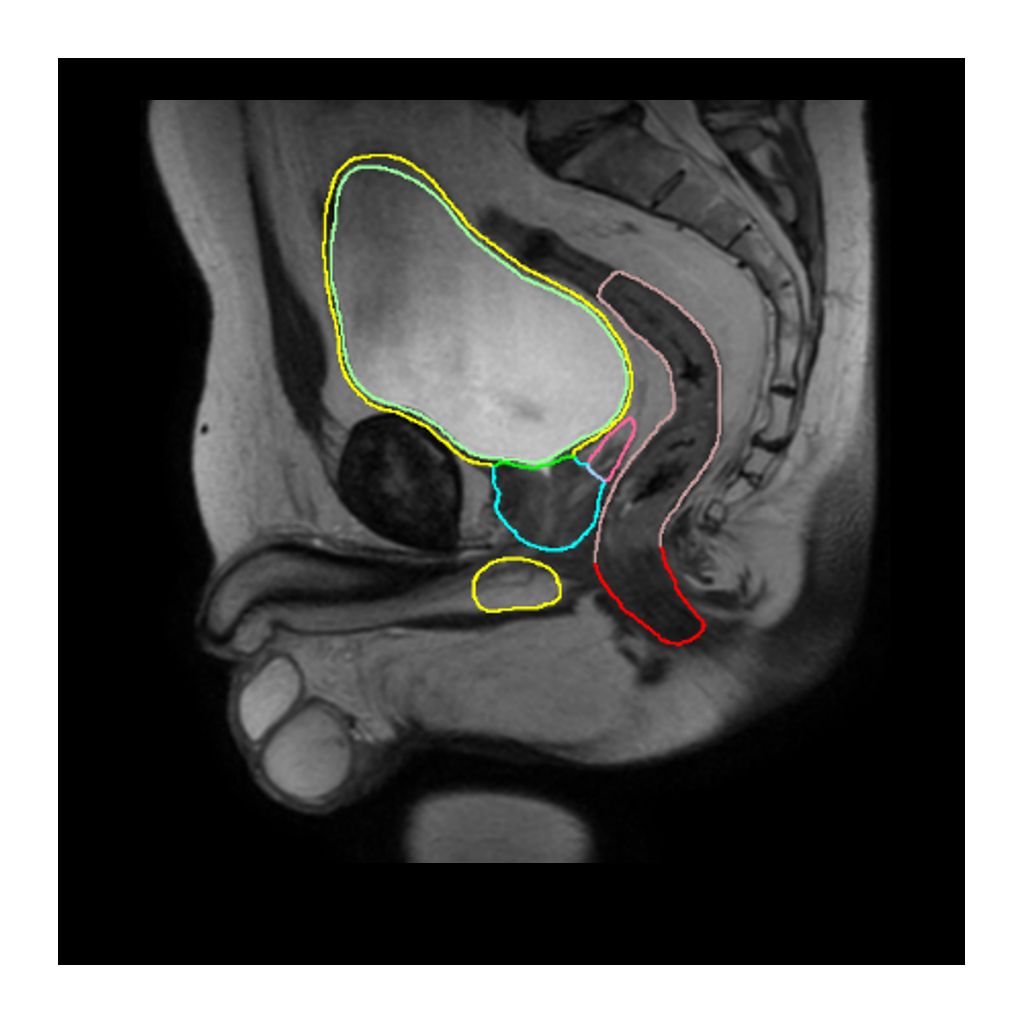

MRCAT Prostate

MRCAT Prostate is intended for radiotherapy planning for prostate cancer treatment. MRCAT Prostate includes auto-contouring, which automatically and quickly creates contours of the prostate and the Organs-At-Risk (OARs), based on dedicated MR sequences.

Onesite web image MRCAT prostate